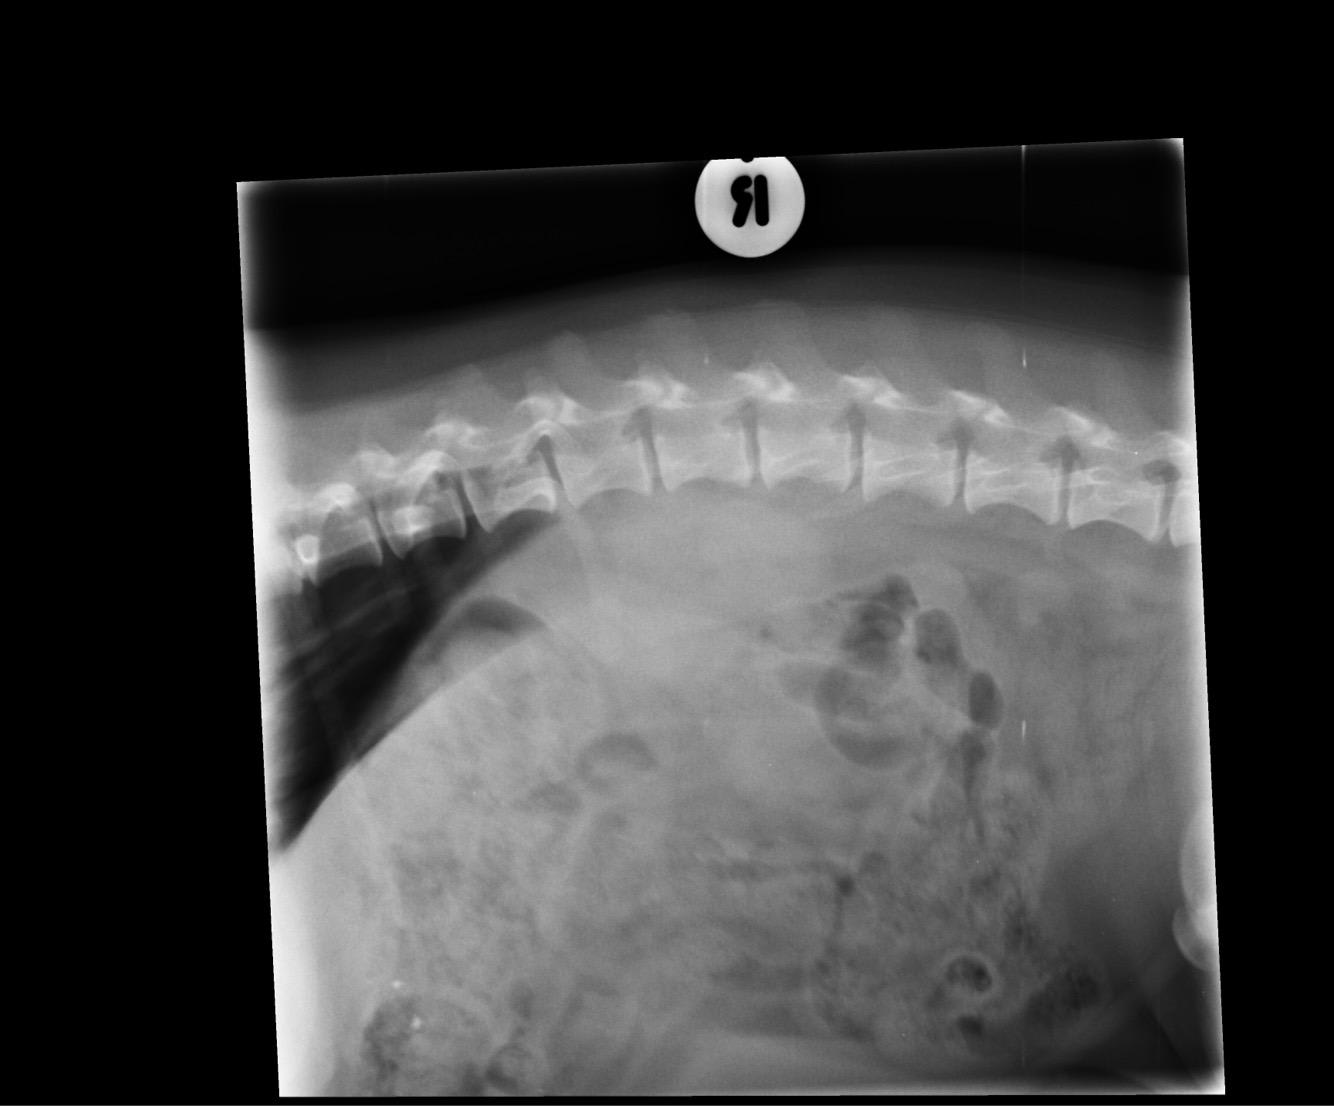

Pet's info: Dog | Dachshund | Male | neutered | 6 years and 6 months old | 20 lbs

Could you please let me know what you think could be in the X-rays? We did a biopsy and I have also attached the report. Please say if you feel it could be removed as well. What would be your next step?

The biopsy results are inconclusive, as they were unable to definitively diagnose what the mass is. This is often the case with bleeding masses in the abdomen - biopsies are often non-diagnostic, due to the fact that there is so much associated hemorrhage, which it looks like is basically all they were able to tell on the biopsy. It's likely that the only way an accurate diagnosis will be achieved is by doing an exploratory surgery of the abdomen. At that time, the mass can be visualized and completely removed (also typically the spleen as well). I recommend x-rays of the chest before this is attempted, as this is the most common site of metastasis. If there is disease in the lungs the prognosis is significantly worse, and this would likely factor into your decision to do the surgery or not.